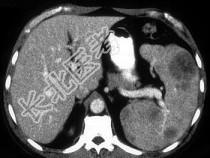

- 单项选择题患者中年,结合图像, 最不可能的诊断为 ( )

A、Gauchers 病(家族性脾性贫血)

B、淋巴瘤

C、转移性黑色素瘤

D、镰刀形红细胞病

E、以上都不是